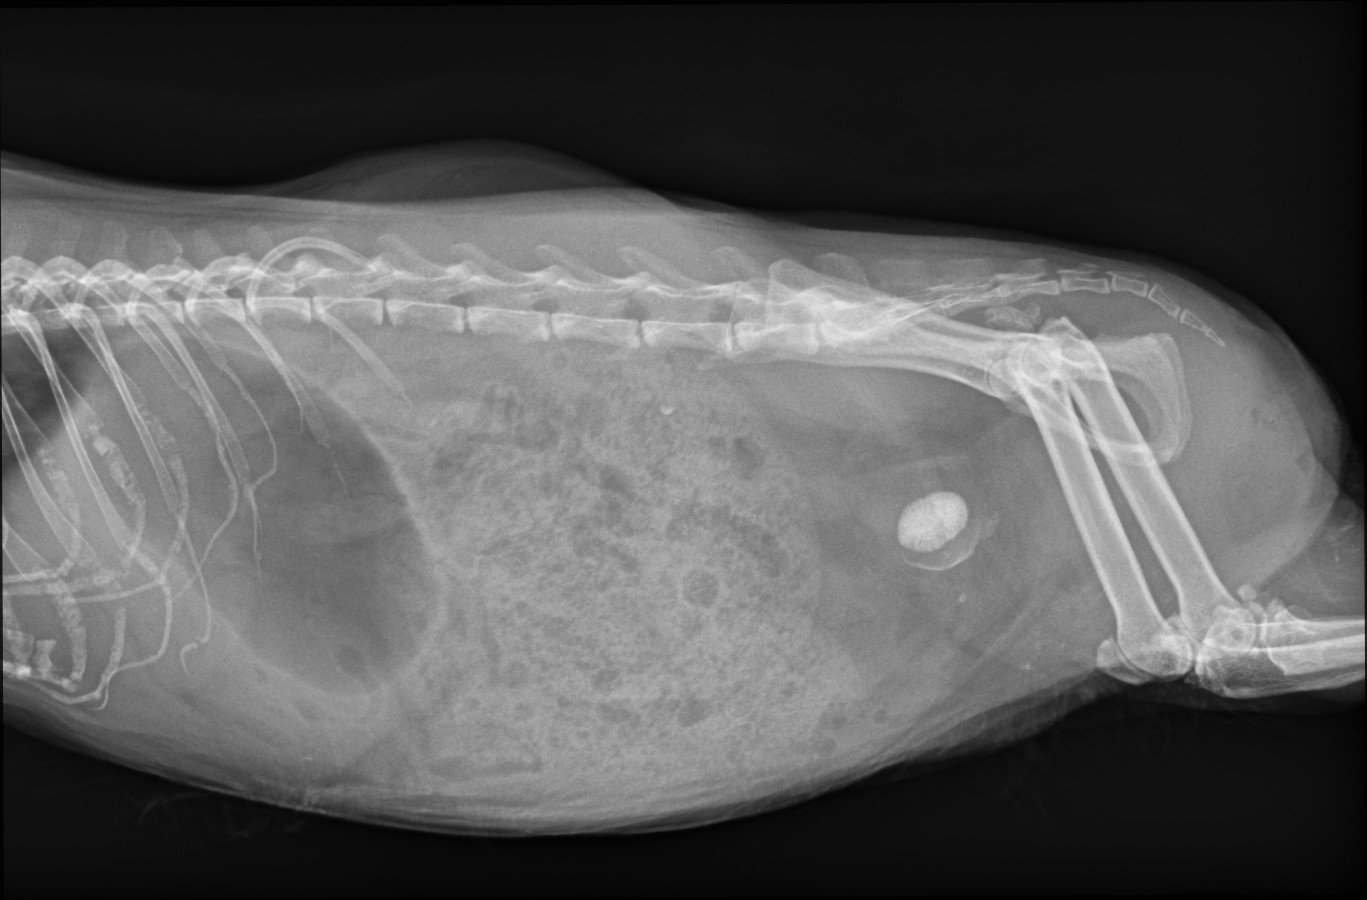

• Wir brauchen ganz dringend eure Daumendrücker morgen. Die kleine Ilse hat sich leider einen Blasenstein eingesammelt und mittlerweile ist ihre Gebärmutter auch gesichert auffällig und mit Flüssigkeit gefüllt.

Morgen wird der Blasenstein entfernt und sie wird kastriert. Es gibt aufgrund ihrer Vorgeschichte, der anspruchsvollen OP und ihres Alters natürlich viele Risiken, aber es gibt keine Alternative.

Yume und ich hoffen sehr, dass sie noch 8 Jahre alt werden darf. Mindestens <3

• Kurzes Update zu Ilse:

Ihr Blasenstein wurde entfernt (Blase eröffnet und Stein raus). Die Gebärmutter war entzündlich Verändert und wurde auch entfernt. Zusätzlich hat Madame noch Zahnprobleme aber das ist jetzt die geringste Sorge.

Sie ist nach etwa 2h OP(also wirklich lange) eigentlich ganz gut wieder wach geworden.

Da ihr Allgemeinzustand aber nicht so gut war und sie auch starke Schmerzen hat, wurde entschieden, sie in der Nacht in der Klinik zu lassen.

Ilse braucht alle Daumendrücker die es gibt damit sie hoffentlich schnell wieder fit wird.🥺